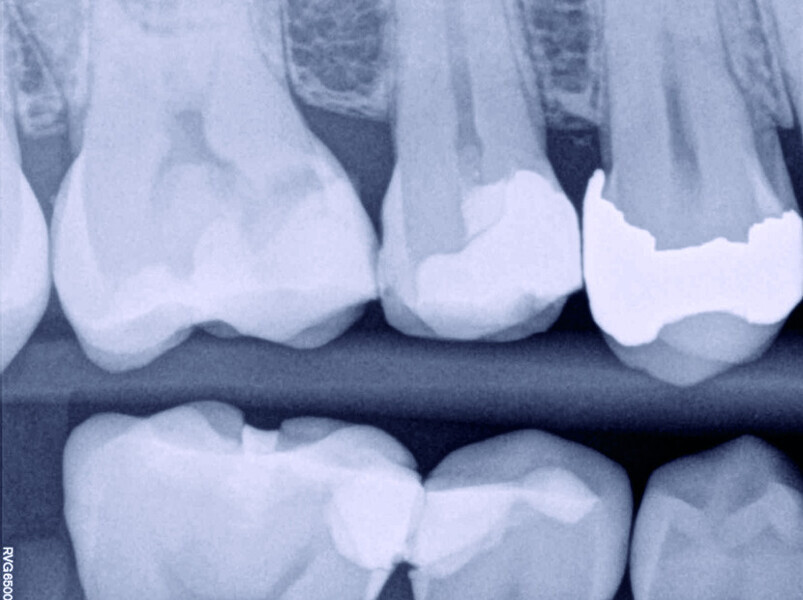

Direct pulp capping as a conservative procedure to maintain pulp vitality